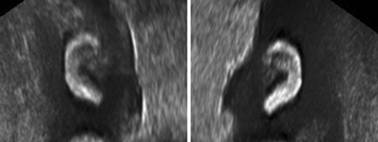

(二)外耳

胎头冠状面和横断面在适当的位置可以显示突出的外耳(图3),由于耳廓复杂的形态,常规二维超声检查除有时可对耳廓上下经进行测量外,难以对耳部的发育进行评估,但三维超声显像检查可以显示外耳的轮廓和结构。已经发现,胎儿耳廓长度(FEL)与孕龄有一定的关系,FEL (mm) = 1.1011 × 孕龄(周)- 9.5089(r 2 = 0.962)。Özdemir 等通过389例16孕周~28孕周胎儿资料获得了FEL与孕龄的关系:FEL =(1.348 × 孕龄(周) - 12.265),并且发现与BPD有良好的相关性(r = 0.962; p < 0.001)。除耳廓的长度外,还要注意耳廓的位置,耳廓过小及位置过低可能与染色体异常有关。

图8-3胎儿耳廓声像图